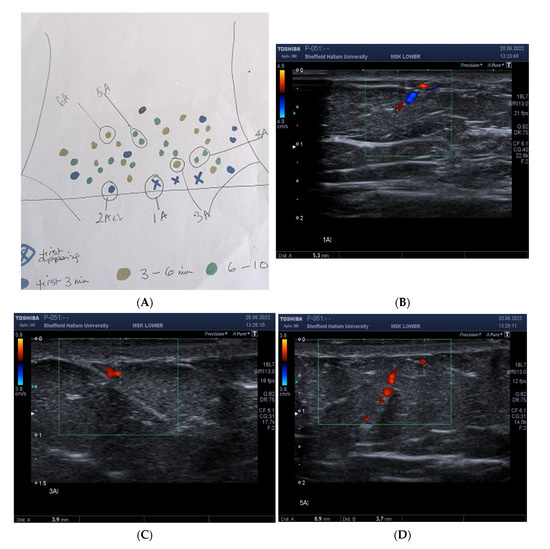

2.5. Correspondence between DIRT Identified ‘Perforators’, Vascular Doppler and Colour and Power Doppler

Correspondence between DIRT Located Hotspots and Independent Measures of Skin Perfusion